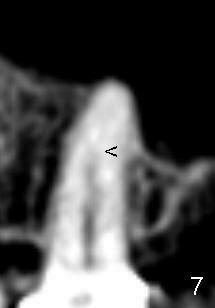

让我们也给左上五作CT检查:这颗前臼齿牙根和根管末端也弯曲(图七),尤其是根管在箭头处突然变细。颊舌侧CT断面证实:根管在接近根尖处分叉(图八红箭头)。各沿着蓝红箭头做两个冠状切片(图九,图十):在根的中部:好像只有一个牙根,根管近远中狭窄,而颊舌侧宽(图九)。在图九'两个箭头之间,根管仿佛有分开倾向,到了根尖(图十,图十'(插图),图十''(图十放大)),牙根也有分开迹象。